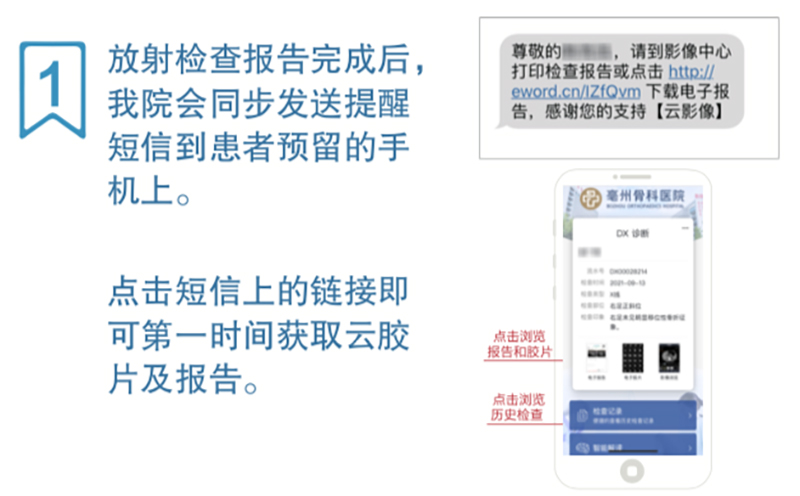

那我们要怎么操作呢?